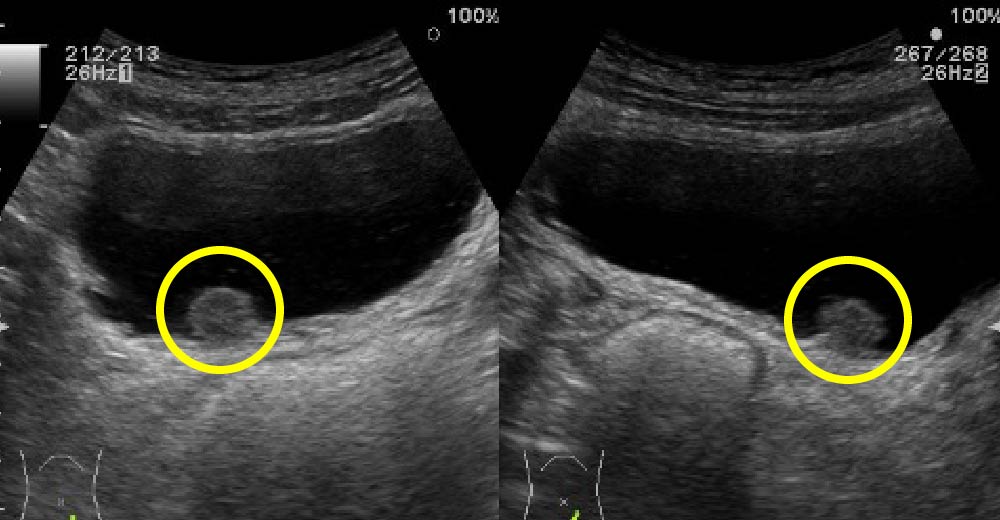

腎細胞がん

腎細胞がん症例です。

エコーで、内部不均一な腫瘤が確認されます。

腎細胞がん 腎細胞がん

造影CTにおいて、不整な造影効果を伴う腫瘤が確認されます

造影早期

造影後期②